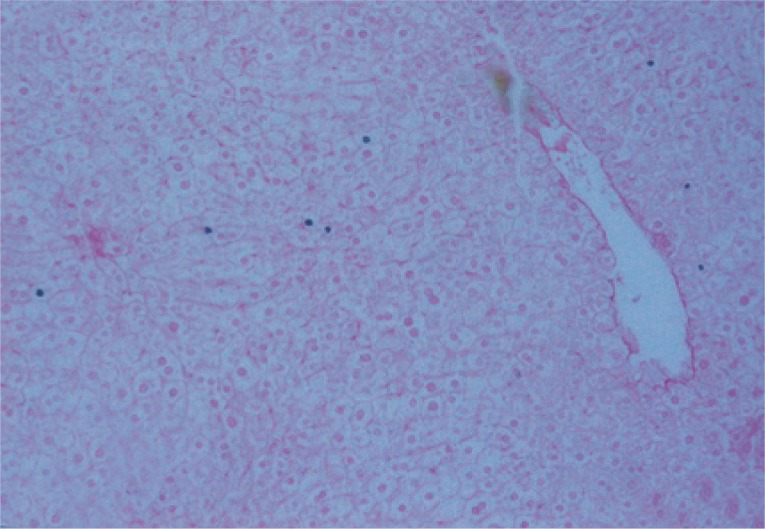

Morphometric studies using Sirius red staining showed significant decreases in the fibrous tissue in BMSCs and BMSCs-HGF-treated groups compared to the infected control group (Figs. 6,7,8,9,10,11,12,13,14,15).

The presence of OV-6 in liver sections of normal, S. mansoni-infected mice, and infected mice treated with BMSCs and BMSCs supplemented with HGF was detected immunohistochemically using monoclonal anti-mouse OV-6 antibodies as a marker for newly formed hepatocytes differentiated from BMSCs. Normal uninfected negative control and S. mansoni-infected control mice showed negative expression of OV-6 in hepatocytes and granuloma cells.

In our study, there was an increase in OV cell number in liver sections of different study groups. Using the anti-mouse OV-6 marker, the liver sections of treated groups either with BMSCs or with BMSCs supplemented with HGF showed positive staining results with increase in the number of cells. Negative reaction for OV-6 marker was noticed in the liver sections of either normal uninfected negative control group or infected untreated groups.